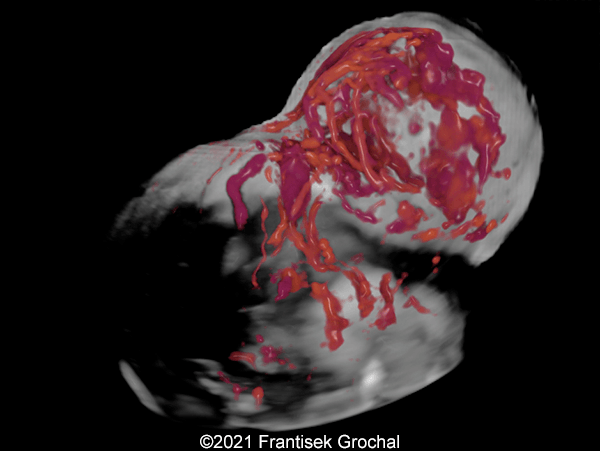

Case Report: A 24-year-old secundigravida, primipara presented to our office at 24 weeks and 6 days of her pregnancy due to a right-sided cranial parieto-occipital mass of the fetus. We obtained the following images.

Our ultrasound images at 24 weeks, 6 days show a highly vascularized, mostly solid mass measuring 58 x 45 x 34mm in the right-parieto-occipital subcutaneous region. Vascular supply of the lesion could be traced to the right vertebral artery. Repeat ultrasound exams done later in pregnancy demonstrated that the size of the mass remained stable with overall mass volume about 58 cm³.